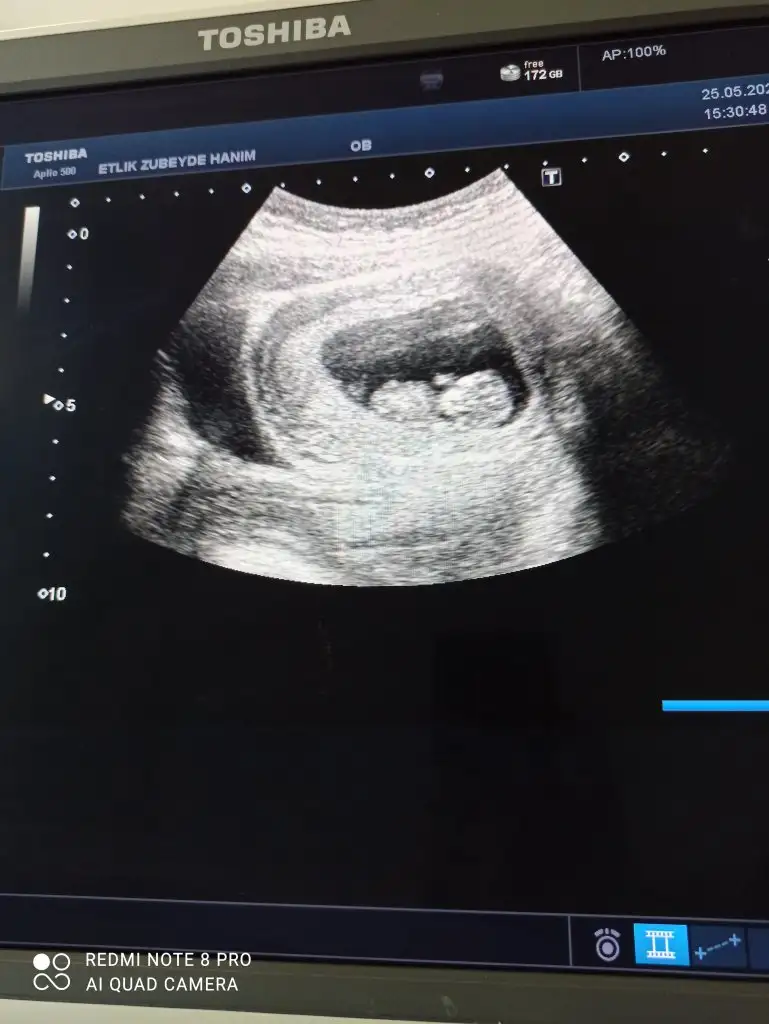

dr soylemeden siz gorun genital nub teorisi ( bebegin cinsiyeti)

Merhaba, buna da bakabilir misiniz?